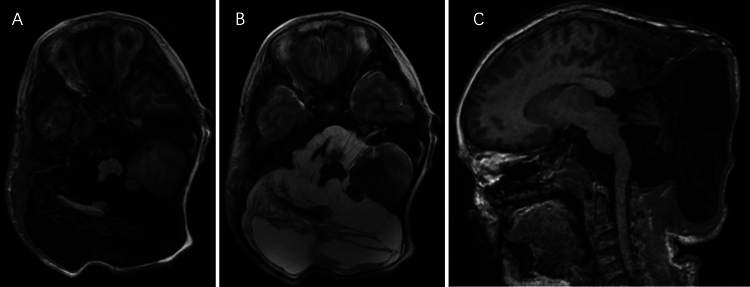

Background: Children with neurofibromatosis type 1 (NF1) rarely develop calvarial defects, and even more rarely do they develop encephalocele and plexiform neurofibroma (PNF).

Observations: The authors report on the repair of osseous defects of occipital bone and encephalocele in a boy with NF1 with a family history of NF1. Targeted medicine was introduced after the repair for unresectable PNF.

Lessons: The etiopathogenesis and treatment of the occipital defects and associated morbidities are discussed. https://thejns.org/doi/10.3171/CASE2561.